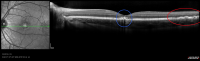

All five patients in the study had a pattern of damage resembling tree branches on both retinas. The authors of the article suggest that eye professionals who observe branch-like retinal damage ask the child or parent about laser play. And because some children are hesitant to talk about laser play in front of their parents, Dr. Tsang suggests talking with the child alone.